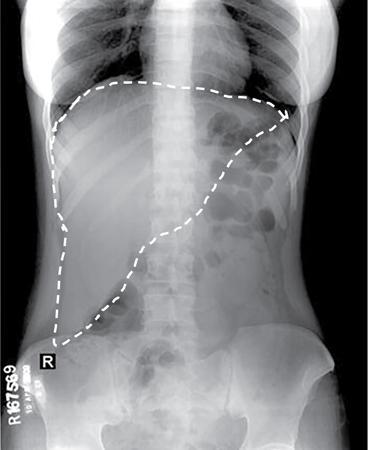

UNDERSTANDING THE ADULT ABDOMINAL RADIOGRAPH: TECHNIQUES AND INTERPRETATION Tanvi Modi Radiography of the abdomen is a common practice for the evaluation of abdominal organs. The anatomy and pathology of digestive, hepatobiliary and genitourinary systems can be assessed using radiographs, either as a stand-alone practice or as a primary imaging modality followed by contrast studies, ultrasound or cross-sectional imaging. In addition, abnormalities of the musculoskeletal or integumentary system can also be deduced on the basis of abdominal radiographs. This chapter intends to give an overview on the techniques and positioning in abdominal radiography as well as interpretation of normal and abnormal features. While superior imaging modalities such as ultrasound, computed tomography (CT), magnetic resonance imaging, capsule endoscopy and the likes have taken over abdominal imaging by and large, radiography still holds a pivotal role in certain situations and conditions, such as: The standard abdominal radiograph is taken in supine position and anteroposterior projection. This is also popularly known as the KUB (kidneys-ureters-bladder) radiograph. Previously, supine as well as erect radiographs were performed in all patients; however, this is not commonly done due to high-radiation dose. For all indications of abdominal radiography, including acute abdomen, supine radiographs are sufficient in terms of radiographic diagnosis, with the exception of perforation for which an erect chest or lateral decubitus radiograph can be performed if there is clinical suspicion. Patient should lie supine on the imaging table with median sagittal plane at right angles to the table and coincident with the midline of the table (Fig. 7.1.1.1). The body is divided into equal right and left halves by the median sagittal which passes through the sagittal suture of the skull. Pelvis should be adjusted so that the anterior superior iliac spines are equidistant from the table top. Gonadal shields, in the case of male patients, should be placed with the upper edge of the shield at the level of pubic symphysis. Although rarely used for female patients, these should be positioned between the anterior superior iliac spines and the pubic symphysis. The centre point of the image receptor should be approximately located at a point 1 cm below the line joining the iliac crests. The X-ray beam should be in a vertical direction, perpendicular to the table top and image receptor at the centre point. Collimation should be such that the soft tissue and subcutaneous region along lateral aspects of the abdominal cavity should be covered within the image. Also, the superior extent involving diaphragm and inferior extent involving the inferior pubic rami is important to look for any lower chest pathologies or any inguinal hernia. 35 × 43 cm (14 × 17 inches) in portrait orientation. On an average, abdominal radiograph exposes a patient to a dose of approximately 1.5 mSv, which is equivalent to 75 chest radiographs or 1/6th dose of a standard CT of the abdomen. The entrance skin dose is approximated to be 4 mGy. At such an effective dose, the additional lifetime risk of fatal cancer is 1 in 30,000. The exposure time is kept short. Patient is asked to exhale completely and hold their breath, with exposure taken at this point of full expiration to ensure imaging of abdominal organs in their natural positions. Modifications of this technique can be made depending on patient habitus and clinical condition. Kilovoltage peak (kVp) should be set to allow adequate visualization of abdominal soft tissue structures as well as semiopaque renal and biliary calculi. Average kVp is set at 70–85 kV. 102 cm (40 inches) Grids are commonly used to reduce scatter radiation. Placement of side marker on the image receptor at the time of radiographic exposure is essential. Bowel pattern depiction should be such that there is minimal lack of sharpness. Standard guidelines for abdominal radiography dictate that the radiograph should extend from the diaphragm up to the level of inferior pubic rami and must include the lateral abdominal wall musculature. The abdomen is divided into four quadrants on the basis of two perpendicular lines (Fig. 7.1.1.7). The vertical line passes through the mid sagittal plane and crosses the umbilicus and symphysis pubis. The horizontal line is a transverse line across the umbilicus at 90 degrees to the vertical line and is situated at the level of L4–L5 intervertebral disc. The quadrants are as follows: Another division system is dividing the abdominopelvic cavity into nine regions using two vertical and two horizontal planes (Fig. 7.1.1.8). The vertical planes, also known as the right and left lateral planes, are parallel to the midsagittal plane between midline and anterosuperior iliac spines on either side. Of the two horizontal planes, the upper transpyloric plane is at the level of lower border of L1 and the lower transtubercular plane is at the level of L5. The nine regions are: On a standard radiograph, the exposure should be such that the stomach, bowel loops, outlines of liver, spleen, kidneys, psoas muscles should be well identified. Also, lumbar transverse processes should be seen. Arch of the pubic symphysis should be visible to evaluate bladder region. A well-centred film without rotation will demonstrate bilaterally symmetrical lower ribs, iliac wings, ischial spines and obturator foramina. Different structures seen on an abdominal radiograph can be classified into five basic densities: Identification of different structures depends on the relative degree of contrast between their densities. The demarcation is clearer in chest and is diminished in abdomen due to relative similar soft tissue density of various structures. On a normal radiograph, relatively large amounts of gas in stomach and colon with minimal small bowel gas can be seen. Further, colonic gas can vary from negligible to extensive, mimicking obstruction pattern; however, usually the gas is enough to delineate colonic haustral pattern. Faecal matter gives a mottled appearance to colonic gas. Short-air fluid levels on an erect radiograph may be seen even in normal cases. The normal appearance of small bowel loops on an abdominal radiograph follows the rule of threes: Stomach is seen in the left upper quadrant and is visualized when distended with air. It is commonly seen extending from T11 to L2 level. Common feature identifying the stomach is the fundal gas which is usually seen as an air fluid level within the gastric lumen. Small bowel loops are distributed to the centre of the abdominal cavity and large bowel loops are peripheral. Duodenum is predominantly situated in right upper quadrant. It extends to left upper quadrant in the region of duodenojejunal flexure. Jejunum occupies the left upper and lower quadrants and is easily identified due to the presence of thick, numerous, closely spaced valvulae conniventes (Fig. 7.1.1.9A). The ileum occupies both lower quadrants and extends into right upper quadrant. Ileum has few and less prominent valvulae as compared to jejunum (Fig. 7.1.1.9B). Ascending and descending colon are retroperitoneal and have relatively fixed positions along lateral aspect of the abdominal cavity on either side. Transverse and sigmoid colon, on the other hand, may have a variable position due to their mobility along mesocolon and redundant pattern. These can be identified with confidence on account of haustrations and faecal matter (Fig. 7.1.1.10). Haustrations are usually well seen in ascending and transverse colon and poorly delineated beyond splenic flexure. Caecum is in the right lower quadrant, though it may be mobile or pulled up. Rectal gas is usually seen in the midline at the level of pelvis and its presence rules out large bowel obstruction. All these positions may vary due to anatomical conditions such as malrotation or pathological conditions, for example volvulus. Liver, spleen and renal outlines cannot be completely traced with precision due to the overlap by bowel loops. On a frontal projection, the liver appears as a triangular structure occupying right and left hypochondrium and epigastric region. Occasionally, the right lobe may be seen extending lower than the right renal shadow. This is a normal variant known as Reidel’s lobe. Gall bladder is situated in the posterior and inferior region of the liver and any pathology of the gall bladder should be looked for in this region. On a lateral radiograph, the gall bladder is anterior to the midcoronal plane. This helps in distinguishing gall bladder calculi from renal calculi, which will be more posteriorly situated. Spleen is seen in left upper quadrant/left hypochondrium, flushed to left lower ribs and left hemidiaphragm. Pancreas is present in the epigastric region (right and left upper quadrants) and is usually not identified in the absence of a pathology. The kidneys are bean-shaped retroperitoneal organs which are seen on either side of the vertebral column and lateral to psoas muscles. Due to the presence of liver on the right side, this kidney is slightly lower in position as compared to its contralateral counterpart. The visualization of kidneys on radiographs is facilitated by the surrounding fatty capsule. Kidneys lie between T11–12 and L2 level, with left kidney 1 cm higher than the right. Psoas muscle shadow can be normally seen along lateral aspect of lumbar spine bilaterally and is mildly concave (Fig. 7.1.1.11). Abdominal wall muscles are not routinely assessed on radiography; however, inclusion of lateral abdominal wall (muscles as well as subcutaneous plane) is a must while performing radiography. The flank stripe or the properitoneal fat stripe is a fat density linear concavity seen along lateral abdominal wall (Fig. 7.1.1.11). It is bound by the paracolic gutters and air-filled ascending and descending colon. All the solid organs in the abdomen are identified due to the fat density outlining them. Distortion of these fat lines helps in identifying organomegaly or focal mass lesions. The dome of urinary bladder is outlined by fat, which aids in differentiating its density from other soft tissue structures of the pelvis. Not all calcifications seen on abdominal radiograph are abnormal. Some may depict age-related changes such as vascular calcifications involving abdominal aorta, pelvic vessels, splenic artery in the region of left upper quadrant. Within the pelvis, phleboliths may be seen and mistaken for urinary calculi. Assessment of lumbosacral spine, iliac bones and femoral heads can be made on the basis of plain radiography. Degenerative changes may be commonly seen. Lower ribs can also be evaluated for pathologies. Dilated small bowel loops with rounded soft tissue density in midline over umbilical region suggests obstruction secondary to umbilical hernia. Pneumoperitoneum must be looked for in all cases of acute abdomen. While erect chest and left lateral decubitus radiographs can detect even 1 mL of free air, there are multiple signs on supine radiograph to suggest this diagnosis, for example Rigler’s sign, falciform ligament sign, football sign (Figs. 7.1.1.24 and 7.1.1.25). Retroperitoneal perforation may demonstrate air outlining psoas muscles and retroperitoneal organs. Small amount of free air may persist in the abdominal cavity up to 3 weeks after surgery, although it usually resolves within a week. Clinical history is important in such cases. Air foci within the bowel wall may represent bowel ischaemia/strangulation. Linear gas patterns in right hypochondrium may be due to two causes, that is pneumobilia and pneumoporta. The former can be seen normally postbiliary surgery, sphincterotomy, ERCP or in the case of abnormal fistulous communication between bowel and biliary tree (Fig. 7.1.1.26A). Pneumoporta (Fig. 7.1.1.26B) is a red flag and warrants further investigation to look for conditions such as mesenteric ischaemia and toxic megacolon. Pneumobilia is more centrally located whereas air shadows in pneumoporta are seen reaching up to periphery of liver. Air foci over renal shadows (Fig. 7.1.1.27), gall bladder or pancreas, in the absence of recent procedural history, suggest fulminant infection and mandate urgent intervention. Central midline calcific foci between T9 and T12 vertebrae can be attributed to calcific pancreatitis (Fig. 7.1.1.28). In the left upper quadrant, areas of calcification seen involving a shrunken spleen may be seen in autosplenectomy. In right upper quadrant, calcified gall stones may be seen. These tend to be small, multiple, uniformly circumscribed and ring-like in appearance with central translucency (Fig. 7.1.1.29A). Mercedes Benz sign, a triradiate pattern of gas lucency, is associated with gallstones. In contrast, renal calculi are more commonly solitary, irregular, of homogenous density, conform to renal calyceal or pelvic outline (Fig. 7.1.1.29B) and are sometimes of staghorn configuration. On lateral view, the gall stones are more anteriorly located as compared to renal calculi, which may be partly superimposed on lumbar vertebrae. Ureteric calculi tend to overlap bony structures such as lumbar transverse processes (Fig. 7.1.1.29B) or sacroiliac joints. Extensive or patchy, curvilinear calcification of gall bladder wall is known as porcelain gall bladder which is often associated with malignant transformation. Calcification involving adrenal glands may be secondary to infection or haematoma, or a congenital condition known as Wolman’s disease where there is bilateral involvement. Discontinuous discrete midline tram track calcification in the abdomen may indicate atherosclerotic changes in abdominal aorta and branch vessels. However, when the calcification is in a globular pattern and seen below the level of L2 vertebra, aortic aneurysm should be suspected (Fig. 7.1.1.30). Appendicoliths, though not commonly seen, may sometimes be detected in right iliac region. Pelvic calcifications: vesical calculi, distal ureteric or vesicoureteric junction calculi, calcified fibroids, ovarian dermoid with tooth-like calcifications (Fig. 7.1.1.31) may be the cause of abdominal pain and should be diligently looked for. Vesical calculi are usually more large and central in location whereas calcification due to fibroids may be more lateral. Schistosomiasis is another cause of bladder wall calcification, as is calcification of bladder tumours. Phleboliths tend to be bilaterally symmetrical, with a lucent centre unlike ureteric calculi. While it is believed that phleboliths are located below the level of ischial spines and ureteric calculi above, this is not always true and should be confirmed with CT. Fluid may collect adjacent to properitoneal fat line, forming a linear soft tissue density separating the fat line from the ascending or descending colon. Hellmer’s sign demonstrates medial displacement of lateral edge of liver (hepatic angle), due to fluid collection or ascites. Gross ascites may appear as generalized abdominal haziness or diffuse increased density of pelvis. Abscesses can involve any solid organ and in such cases may be difficult to demonstrate on plain radiography alone. Enlargement of organ or faint gas densities within can be suggestive of the same. In the case of peritoneal abscess, mottled density due to air, fluid and necrotic contents point towards this diagnosis, especially in right iliac fossa in association with appendicitis. Retroperitoneal abscess, similar to any retroperitoneal mass, may cause displacement of retroperitoneal structures (Fig. 7.1.1.32). Subdiaphragmatic abscesses may show concomitant ipsilateral pleural effusion (Fig. 7.1.1.33). These should be differentiated from Chilaiditi syndrome. Fluid and soft tissue lesions present with the same density on radiographs. While it is difficult to characterize the lesion and organ of origin, clues for the same can be provided by organomegaly (Fig. 7.1.1.34), distortion of fat surrounding solid organs, displacement of bowel loops or solid organs. For example, a retroperitoneal lesion may cause anterior or inferior displacement of kidney, a pelvic mass may cause upward displacement of small bowel loops. Different densities such as fat or calcification may help in identifying organ of origin (e.g. fat and tooth densities seen in ovarian dermoid). Convexity of margins of psoas muscle on an abdominal radiograph can be due to haematoma, abscess or intramuscular tumour. Radiographs are performed for the initial diagnosis of foreign body in the abdomen including type, number of foreign bodies, location, size and shape (Fig. 7.1.1.35). Radiolucent foreign bodies such as wood, plastic, chicken bones will not be easily identified on radiography. Low kVp (65–70 kVp) can increase contrast and help identify these objects. In addition to an abdominal radiograph, chest radiography is also performed to exclude aspiration or oesophageal location of foreign body. Ingested or introduced foreign bodies may cause complications such as obstruction, perforation, fistula formation and sepsis. Hence, once their presence is confirmed, follow up radiography must be performed until they are eliminated. One must look for fractures/dislocation injuries involving the vertebrae or pelvic bones, especially after history of trauma. Lucent expansile lesions or sclerotic bony deposits which represent neoplasms, absent pedicle sign in cases of metastasis, metabolic bony changes such as rugger jersey appearance, Paget’s disease, arthropathies such as ankylosing spondylitis with bamboo spine appearance and sacroiliitis (Fig. 7.1.1.36) are some of the conditions which may be diagnosed based on an abdominal radiograph. Overlap of bowel loops over iliac blades may lead to a misdiagnosis of lucent lesions and should be evaluated with caution. Basal pneumonia may be the cause of acute abdominal pain and should be looked for in abdominal radiography. Similarly, pleural effusion, pericardial effusion, calcified pleural plaques, achalasia, interstitial fibrosis are few other findings that can be seen in lower chest on an abdominal radiograph. Basilar atelectasis can give a deceptive appearance of pneumoperitoneum (Fig. 7.1.1.37). Surgical clips, commonly in right hypochondrium after cholecystectomy, drainage tubes, ventriculoperitoneal shunts, femoral line catheters, IVC filters, stents (vascular, renal, biliary) (Fig. 7.1.1.38), stoma bags, contraceptive devices are some structures that may be seen in an abdominal radiograph. Correct knowledge of patient history and normal locations of these structures prevents misdiagnosis. Certain artefacts may be projected upon the radiograph due to surface structures such as trouser buttons, body piercing, sequins over clothing and should not be considered as a pathology. Multiple skin surface nodules in cases of neurofibromatosis, soft tissue focal swellings, such as abscesses, lipomas, haematomas, desmoid tumours and malignant lesions may be incidentally seen on radiography. These can be further evaluated using ultrasound or CT. Subcutaneous emphysema is another finding that may be seen in lower abdominal wall secondary to retroperitoneal perforation or diffusely along abdominal wall in the case of bowel perforation (Fig. 7.1.1.39). Foreign bodies such as bullets and pins may be seen lodged in abdominal wall. A systematic approach to abdominal radiographs is important for accurate diagnosis as follows: Despite the development of newer techniques for imaging of the abdomen, plain radiography still holds an important place in the initial assessment of acute abdomen. Positive and negative findings on an abdominal radiograph can direct further investigation. Ideal positioning, recognition of normal appearances and keen scrutiny for pathologies is a sine qua non for radiologists reading a plain film of the abdomen. OESOPHAGOGRAM Padma V. Badhe, Vikram Reddy, Sultan Moinuddin Shaukatali, Zillani Alam, Ravi Varma, Abhishek Bairy, Dasari Ravikiran, Revati Tekwani, Soniya Patankar, Megha Nair, Gautham Shankar Oesophagogram is the process of obtaining radiological images and simultaneous motion recording to evaluate function and disorders of pharynx, oesophagus and proximal stomach. Oesophagogram is usually done primarily to evaluate dysphagia. Some of the common indications are oesophageal motility disorders, strictures, gastro-oesophageal reflux disease (GERD) and suspected masses. It can also be used to detect uncommon anomalies like vascular rings/slings and aberrant anatomy. It also helps to evaluate further in cases where there is inability to pass upper GI scope. Double-contrast oesophagogram is mainly indicated in early mucosal disease like erosion, polyp, infection and tumours. If a motility disorder is suspected, dynamic technique (e.g. videofluoroscopy) is used for dysphagia or aspirations in cases of stroke, neuromuscular disorders, post head and neck surgery or radiation. Barium oesophagogram is contraindicated in suspected cases of perforation and tracheoesophageal fistula, aspiration, rarely if there is hypersensitivity to barium suspensions. It is also contraindicated in suspected oesophageal perforation where a water-soluble contrast agent is more suitable. However, ionic water-soluble contrast agent is better avoided in cases of aspiration or fistula with airway. The contrast examination of the pharynx is dangerous in cases of acute epiglottitis and must be ruled out on plain radiograph. An 80% w/v barium suspension is used in full column views. However, 200%–250% w/v barium suspensions is usually required for mucosal relief films. The barium sulphate mixture is fed to the patient either by spoon, by glass, or through a drinking straw, depending on its consistency. In videofluoroscopy, the pharyngeal phase of swallowing is usually safer with barium pudding than with thick barium and safer with thick barium than with thin barium. However, if the major abnormality is poor pharyngeal contraction leading to stasis in the piriform sinus (and epiglottic tilt is normal), a thin liquid is safer. Epiglottic motility is better assessed with thin barium because thick barium often obscures the epiglottic tip. Fluoroscopic equipment capable of cine fluoroscopy and capability for rapid sequence spot images (high frame rate) is needed for this examination, Barium suspension, straw, glass, Lead apron and radiation protective equipment. The patients are instructed to fast after midnight before the day of the examination. The pharynx should be made as dry as possible during the examination as high-density barium adheres to dry pharyngeal mucosa. Activities like smoking, chewing gum and lozenges must be abstained before the procedure as they impair barium coating by increasing the salivary secretion. Regular oral medications must be taken with sips of water; however, insulin must be skipped on the morning of examination. The major principles of a good oesophagogram includes mucosal coating, distension and projection. A routine oesophagogram consists of screening of the oral, pharyngeal and oesophageal phases of swallowing, single and double-contrast examination of pharynx, single contrast, double-contrast and mucosal relief views of the oesophagus. In cases of dysphagia, the examination is tailored depending on whether the symptoms are either pharyngeal or oesophageal and initial fluoroscopic findings. If patients’ symptoms are suggestive of oral or pharyngeal disorder then pharynx is evaluated first. Similarly, if patient is suspected to have thoracic oesophageal disease then, double-contrast examination of the oesophagus is performed before the pharyngeal evaluation. During an oesophagogram the positioning of the patient varies according to the type of examination (Table 7.1.2.1).